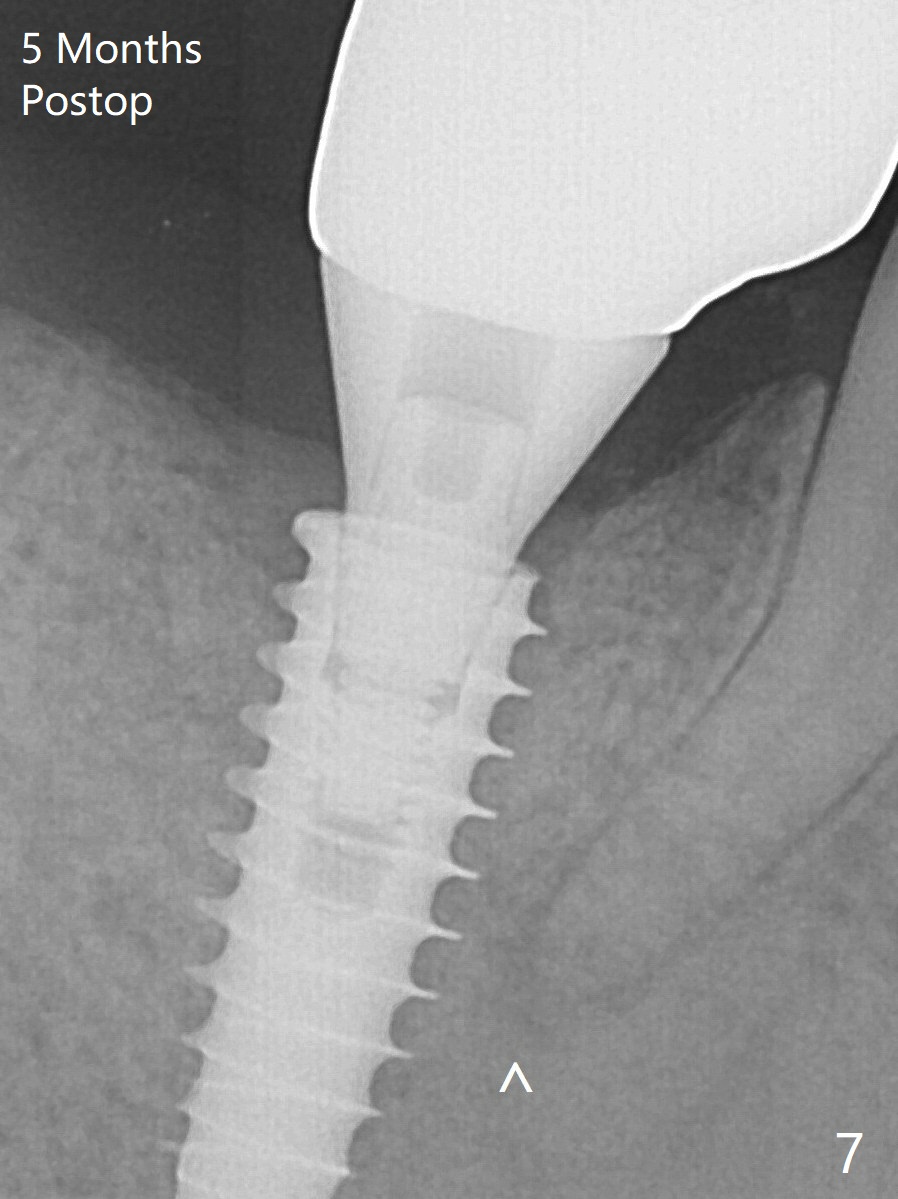

Bone graft seems to sink down and becomes denser 3 months postop (Fig.6 arrow). The bone continues being denser 5 months postop (Fig.7). There is periapical radiolucency of the tooth #29 (^).